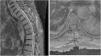

El carcinoma de células de Merkel es un tumor cutáneo maligno poco frecuente, originado a partir de las células neuroendocrinas de la epidermis, denominadas células de Merkel. Presenta un pronóstico infausto cuando la enfermedad es diseminada. Dentro de las metástasis a distancia, la localización espinal es muy poco frecuente y no existe un consenso en cuanto a su manejo. Presentamos el segundo caso descrito en la literatura hasta el momento de afectación metastásica espinal por carcinoma de células de Merkel en paciente inmunodeprimido.

Merkel cell carcinoma is a rare epidermal malignant tumor arised from neuroendocrine epidermal cells, called Merkel cells. Prognosis is poor when tumor spreads to distant locations. Among metastases sites, spinal is not frequent at all and its management remains controversial. We present the second reported case of spinal metastases from Merkel cell carcinoma in an immunosuppressed patient.